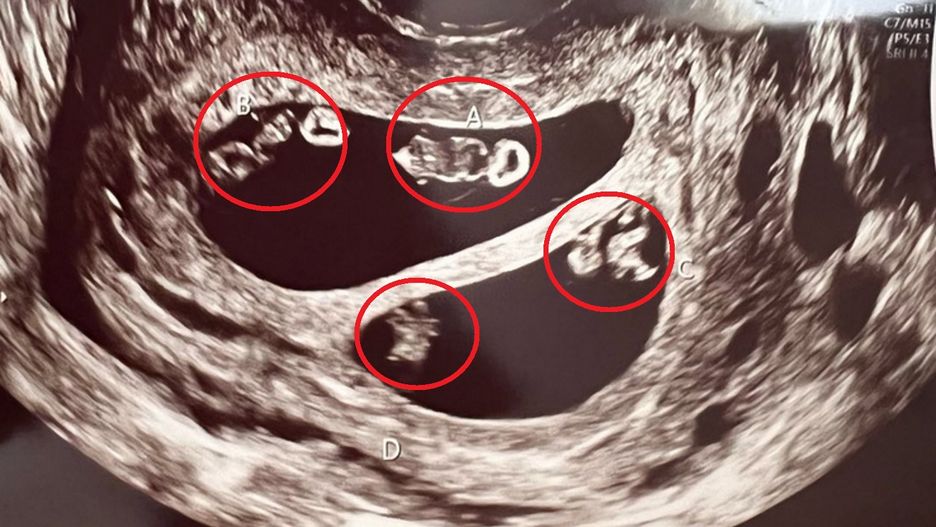

Informacja o bliźniakach wcale nie zdziwiła Ashley. Jednakowo w jej rodzinie, jak i rodzinie jej partnera byli bliźniacy. Jednak gdy kobieta dowiedziała się, że jest w ciąży z dwiema parami bliźniąt jednojajowych, zaniemówiła.

W jej brzuchu było czworo dzieci w dwóch łożyskach. Ashley wspomina, że technik radiolog musiała opuścić pomieszczenie, w którym wykonywane było USG, by upewnić się, czy się nie myli i wygooglować, czy taki przypadek w ogóle jest możliwy.

Dr Ahmet Baschat, profesor w szpitalu Johnsa Hopkinsa w Baltimore powiedział tygodnikowi "People", że taka ciąża zdarza się raz na 10 milionów. Dzieje się tak, gdy w tym samym czasie są zapłodnione dwa jaja, a następnie każde zapłodnione jajo ponownie się dzieli. W przypadku ciąży Ashley każde zapłodnione jajo jest we własnym łożysku. W taki oto sposób kobieta urodziła dwa zestawy identycznych bliźniąt.